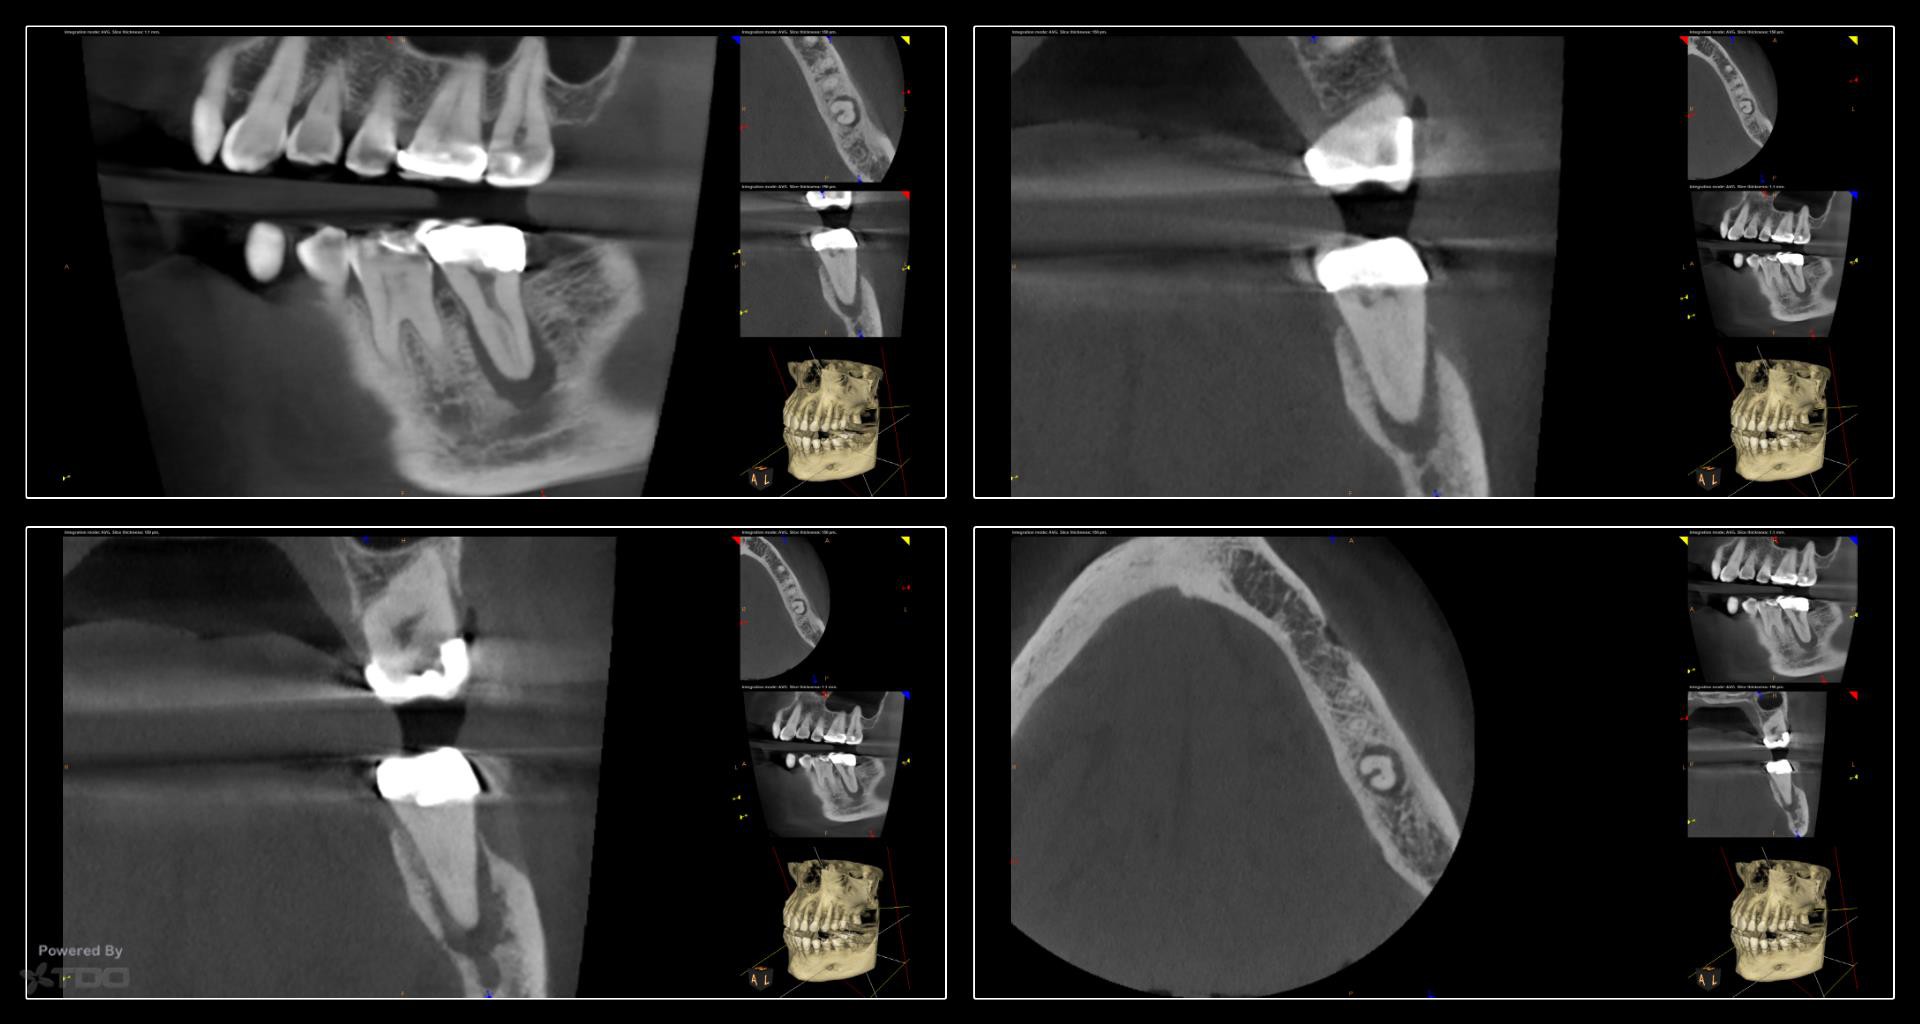

Collage-232332-Page00

This was a finish from last week.  The largest file used was a 20.  The innovation of the heat treated files allow us to be more conservative from the access to the instrumentation.